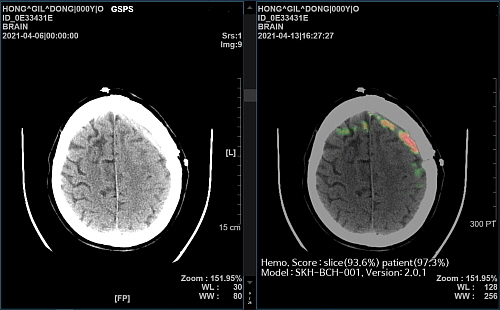

‘메디컬 인사이트 플러스 뇌출혈’은 뇌 CT 영상을 수초 내로 분석해 출혈 위치와 이상 여부를 의료진에게 바로 알려주는 AI 뇌출혈 진단 보조 솔루션이다.

이번 연구에서 비영상의학전문의들이 AI 뇌출혈 진단 보조 솔루션의 도움을 받으면 영상의학전문의 수준의 진단 결과 정확도를 얻을 수 있다는 점이 입증됐다는 것이 회사 측 설명이다.

즉, 의료진을 전공별로 ▲비영상의학전문의 ▲영상의학전문의 ▲신경두경부 영상의학전문의 그룹으로 나누어 AI가 뇌출혈 진단에 미치는 영향을 분석한 결과,

모든 그룹에서 AI의 도움을 받았을 때 진단 정확도의 향상을 보였고, 특히 비영상의학전문의의 경우 가장 큰 도움을 받을 수 있는 것으로 나타났다는 것.